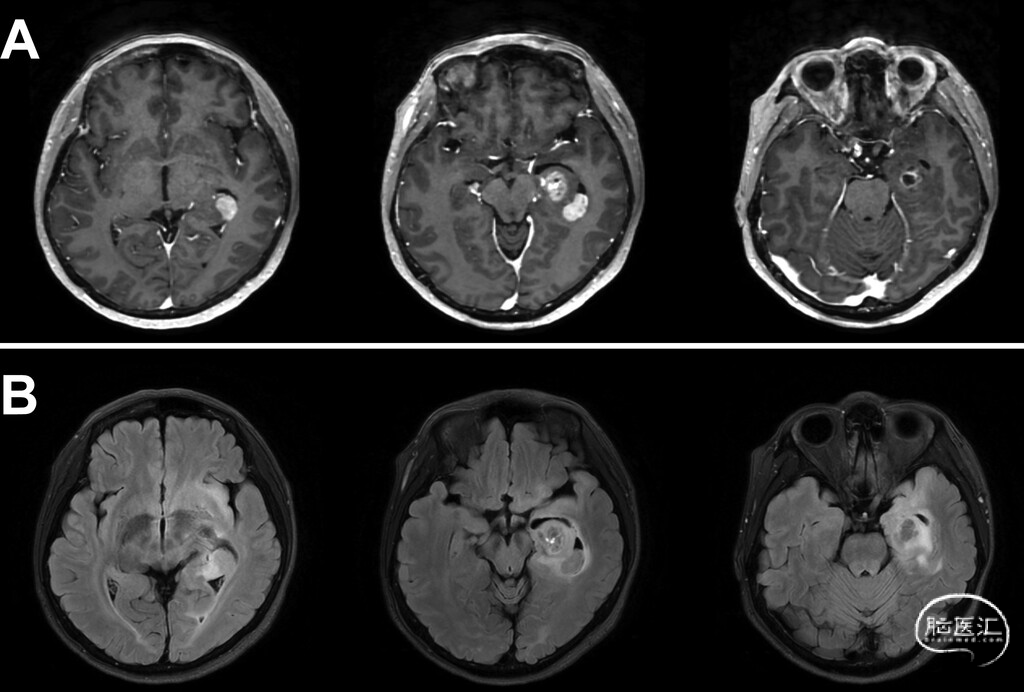

● 患者为既往癫痫控制良好的53岁女性,因癫痫复发且记忆力进行性下降就诊。MRI显示,左侧颞叶内侧及海马区可见不均匀强化肿块,周围T2-FLAIR高信号区延伸至颞前叶、眶额区及脑岛,符合高级别胶质瘤表现(图1)。

图1:术前MRI。A:钆增强轴位T1加权像显示,左侧额颞区存在不均匀强化肿块,中心位于颞叶内侧(含海马结构)及颞叶外侧。肿瘤呈不规则强化,伴中央坏死及瘤周水肿。B:轴位FLAIR像显示,左侧额叶及颞叶见广泛T2-FLAIR高信号,浸润性信号改变延伸至眶额区及周围白质。